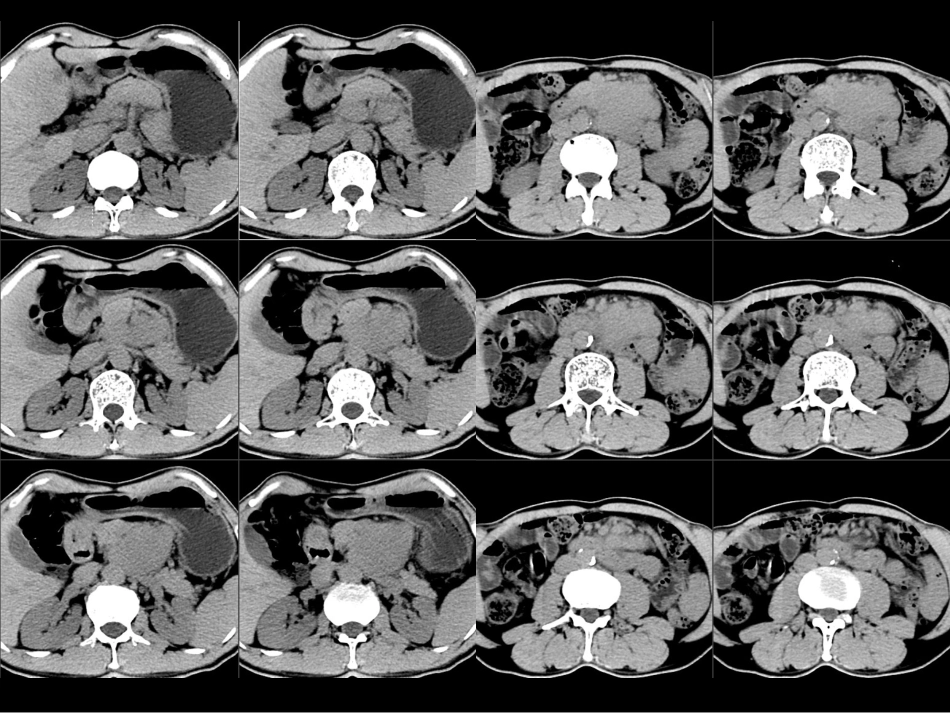

病例1病例2病例3Castleman病CT表现小讲座福建医科大学附属第一医院影像科孙辉红(sunhvhong@sina.com)病例1•男,58岁,反复左上腹胀痛半年余。肿瘤标志物正常•*1甲胎蛋白(AFP)1.5800-13.6ng/ml电化学发光法•*2癌胚抗原(CEA)2.10-5.2(吸烟者:0-6.5)ng/ml电化学发光法•3糖类抗原125(CA125)5.7600-35U/ml电化学发光法•4糖类抗原15-3(CA15-3)10.2300-25U/ml电化学发光法•5糖类抗原19-9(CA19-9)1.4200-34U/ml电化学发光法•6糖类抗原72-4(CA72-4)•淀粉酶(AMYL)>35632bg32-641U/L干化学强生诊断及鉴别诊断征象:平扫密度均匀,无出血、坏死、钙化。增强:动脉期明显强化,门脉期及实质期均匀持续强化。周围情况:胰腺、十二指肠、血管诊断??•定位:胰腺、腹腹后•定性:富血供肿瘤•胰腺神经内分泌肿瘤•副神经节肿瘤(嗜铬细胞瘤)•间质瘤•恶性淋巴瘤•透明血管型Castleman(巨淋巴结增生症)病例1:男,58岁CT0372461B1.(腹膜后淋巴结)Castleman病伴累及胰腺组织,胰腺腺泡破坏伴嗜酸性变,部分淋巴滤泡增生活跃。2.(另送小肠一段)Castleman病累及肠壁浆膜层及肌层,病变周围肠壁肌层间血管扩张,似血管瘤样表现,小肠上、下切端未见明显病变。免疫组化:CD34、SMA、D2-40:血管(+);CD3、CD20、Ki-67、CD10、Bcl-2、Bcl-6:表达模式未见显著异常;CD38浆细胞(+)。胰头区见巨大占位,约8.2cm×6.8cm,病灶境界尚清,可见分叶,边缘见点状钙化,密度不均匀,增强后呈明显不均匀强化,胰腺头部部分消失。胰管和胆管均不扩张,胰体部胰管旁尚可见一0.6cm左右小囊状低密度灶。十二指肠向右侧推移。胰头部占位,考虑神经内分泌肿瘤,胰体部小囊肿(胰十二指肠切除标本)恶性间质瘤.梭形细胞型,细胞略丰富,轻到中度异型,散在异型明显的细胞,局灶区查见肌层浸润和粘膜浸润,核分裂约0-1个/50HPF,形态学提示为低度恶性间质瘤,切缘未见肿瘤累及.胃旁淋巴结4枚,未见肿瘤转移.建议检测基因突变状况.酶标((09-N5752):CK广(-),VIM(100%++),SMA(10%+),DES(-),Ki-67(小于1%+),CD117(100%++),DOG-1(100%++),CD34(100%+),Nestin(100%+),DES(-),VEGF(-),VEGFR1(-),VEGFR2(-),VEGFR3(+/-),S100(70%+).恶性间质瘤胰头后方占位,考虑为十二指肠来源间质瘤可能大,胰尾占位,考虑导管内乳头状粘液瘤可能大,胰尾MT伴后腹膜淋巴结转移不能完全除外右后腹膜巨大肿瘤,位于十二指肠、胰头后方,与下腔静脉,左右肾静脉、肝动脉、门静脉、胆管关系密切,直径约15厘米。作Koch切口翻起十二指肠,暴露肿瘤右侧及下侧部分,打开小网膜孔,分离肿瘤和肝动脉、门静脉、胆管之间粘连及交通小血管。分离肿瘤和十二指肠、胰头之间粘连及交通小血管,肿瘤根部位于下腔静脉,左肾静脉之间,予完整切除。术中触动肿瘤,患者血压一度升高至200mmHg以上,切除肿瘤后血压至正常水平,为安全起见,患者送ICU继续治疗。冰冻病理为副神经节瘤。(胰头)镜下肿瘤组织呈腺泡样巢状排列,结合酶标,考虑副神经节瘤伴部分区细胞丰富,细胞轻度异型,纤维包膜内个别脉管可见瘤栓,建议临床密切随访。酶标(2010-N4391):CD56(+),SYN(-),CHG(+),S100(+),CD10(-),VIM(+),B-cat(+),KI67(-),CK广(-),Keratin(-),ACTH(-),VIP(-),GLV(-),GS(-),SENO(-),Insnlin(-),PP(-),Some(-),EGFR(-)。副神经节瘤Castleman病(Castleman’sdisease,CD)•又称巨淋巴结增生症或血管淋巴性滤泡组织增生,是一种罕见的以不明原因淋巴结肿大为特征的慢性淋巴组织增生性疾病.•临床上按肿大淋巴结的分布分为单中心型(UCD)和多中心型(MCD)。•病理学按组织学特征分为透明血管型(hyaline-vasculartype,HVT)、浆细胞型(plasmacelltype,PCT)和兼有二者特征的混合型。CD临床分型•CD是一种少见的良性淋巴结增生性疾病。病因不明,可能与慢性炎性反应、免疫功能异常等因素有关。•CD按组织病理学标准分为HV型和PC型•HV型占75%~90%,PC型占10%~25%,混合型占1%~4%。病理表现•透明血管型CD镜下表现为淋巴滤泡增生伴生发中心形成,大量小...